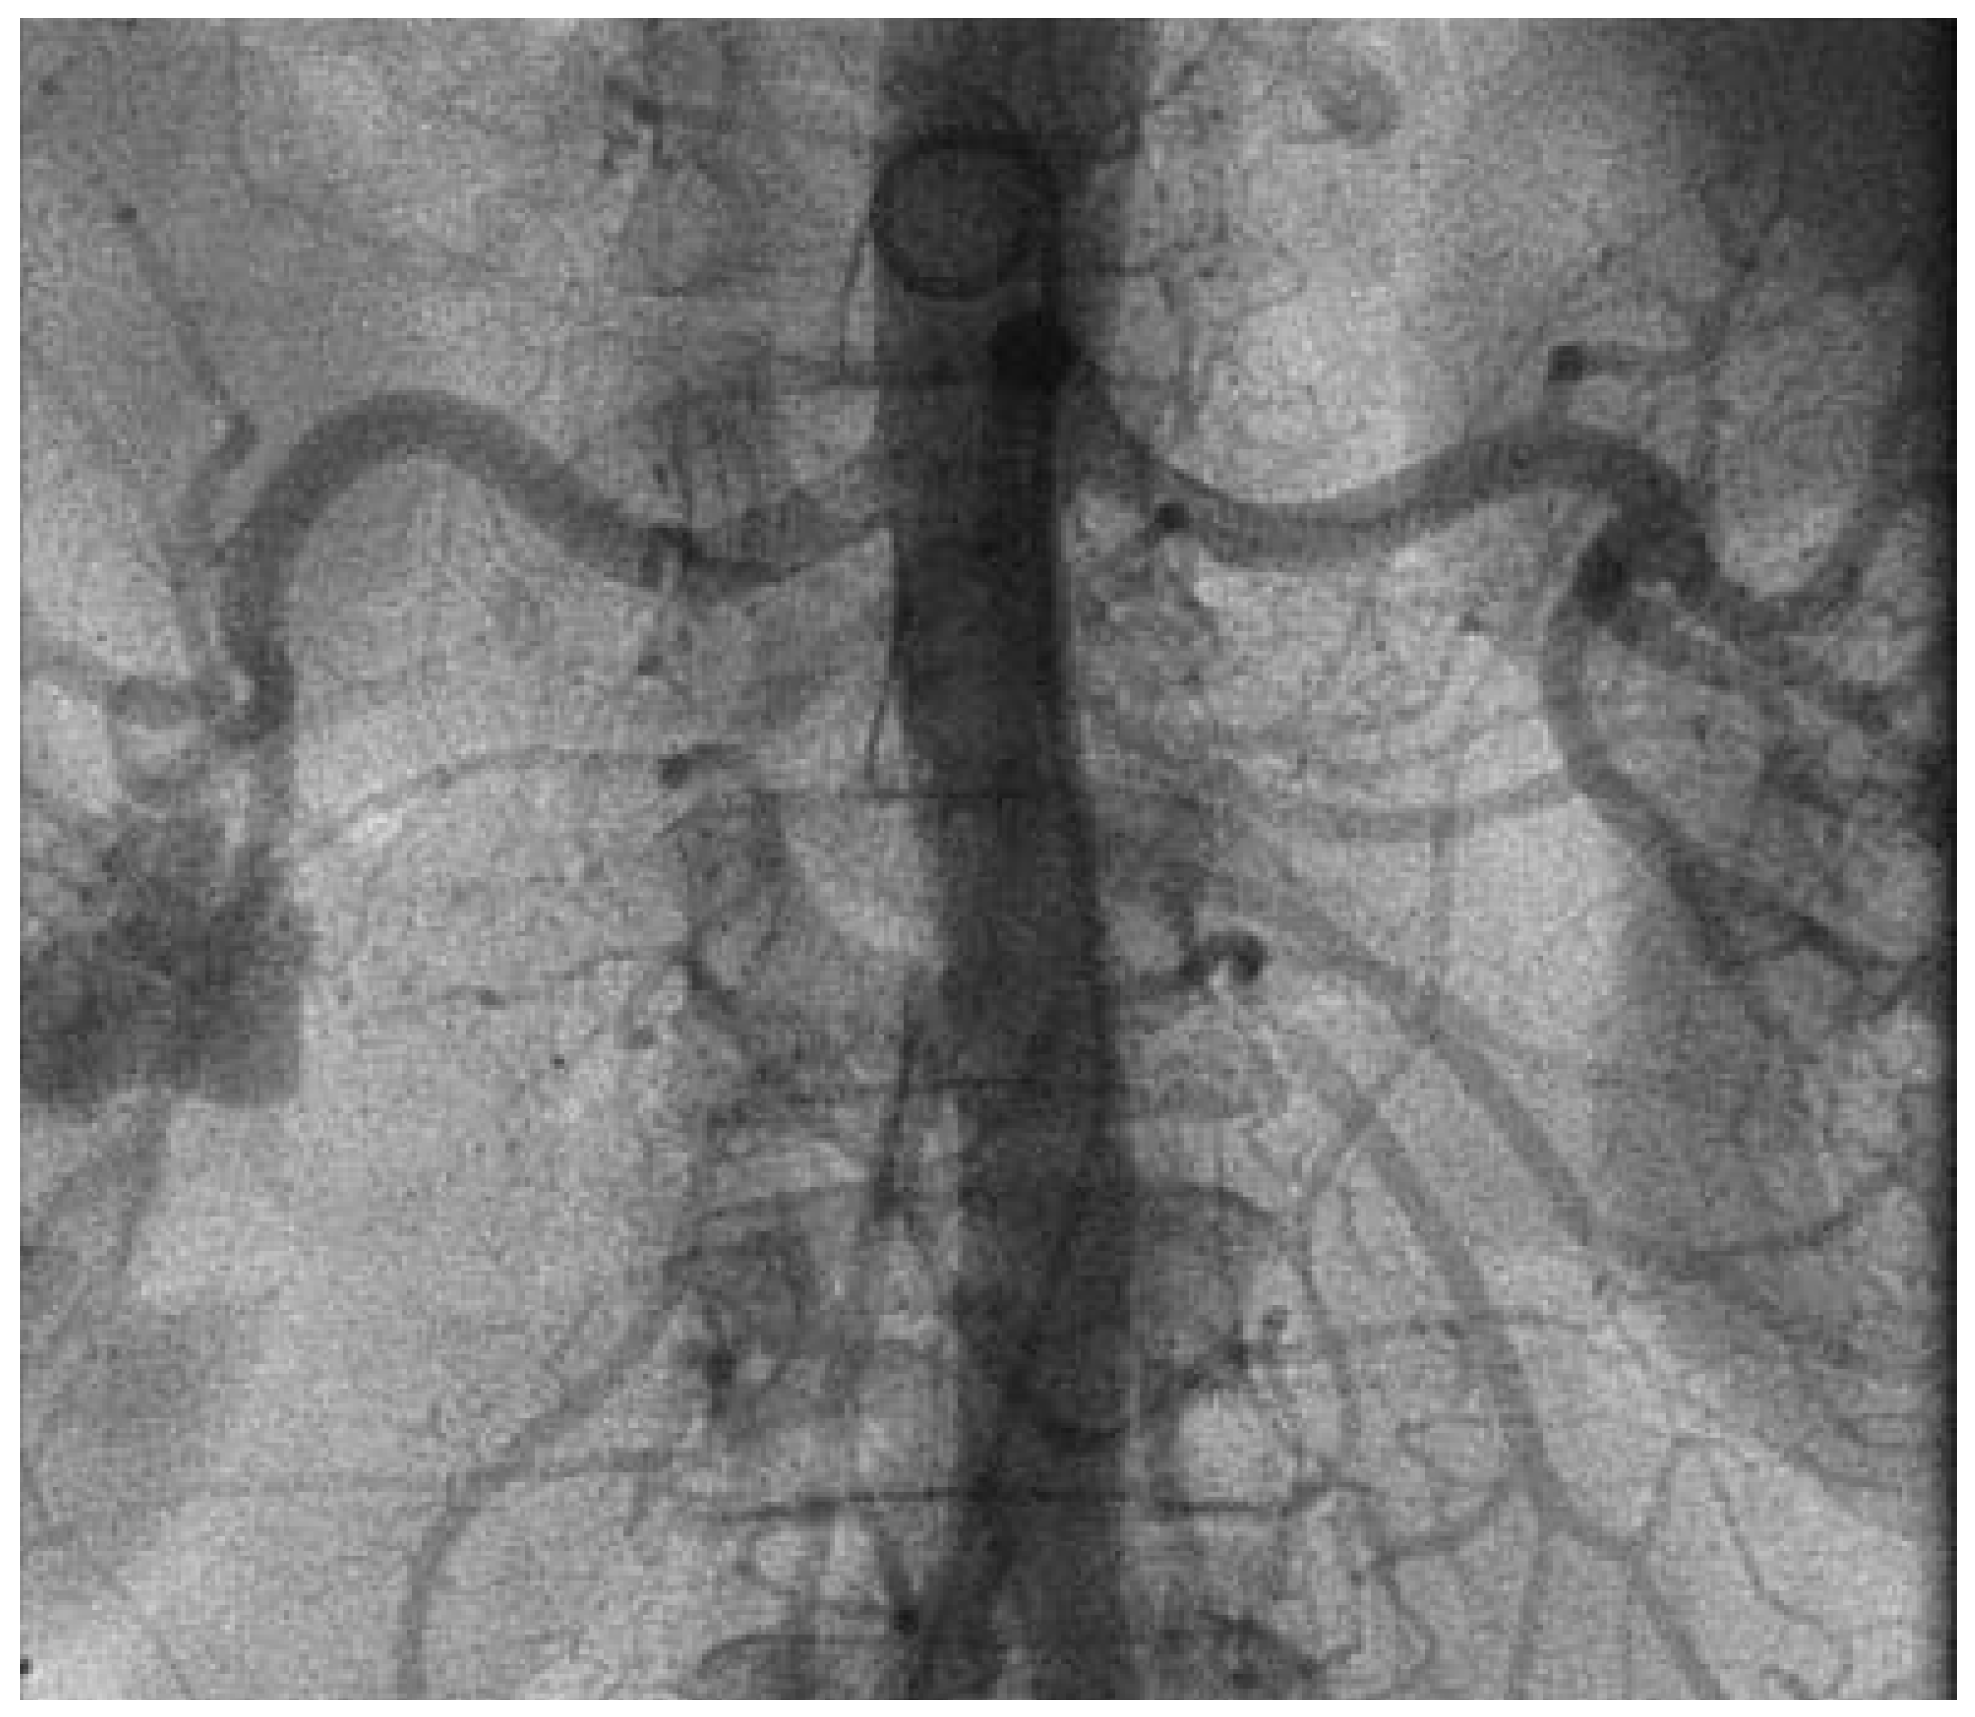

Abbildung 1.

Herz-MRT. A Darstellung des Herzen in der kurzen Achse: a = Wanddicke des Kammerseptums (normal <11 mm); b = Dicke der Lateralwand (normal <11 mm). B Vierkammerblick des Herzens.

Wir berichten über eine 66-jährige Patientin mit langjähriger therapieresistenter arterieller Hypertonie. Trotz antihypertensiver Therapie mit 5 Medikamenten konnten keine befriedigenden Blutdruckwerte erzielt werden. Subjektiv berichtete die Patientin von regelmässig wiederkehrenden Kopfschmerzen. Neurologische Abklärungen erbrachten keine eindeutige Ursache. Als Äquivalent eines hypertensiven Endorganschadens zeigte sich magnetresonanztomographisch eine linksventrikuläre Hypertrophie (Abb. 1). Die während der klinischen Verlaufskontrollen gemessenen Blutdruckwerte betrugen im Durchschnitt im Sitzen 175/88 mm Hg und im Stehen 169/86 mm Hg. Die initiale Langzeitblutdruckmessung zeigte Blutduckwerte im Tagesdurchschnitt von 154/77 mm Hg bei einer mittleren Herzfrequenz von 64 pro Minute (Abb. 2).